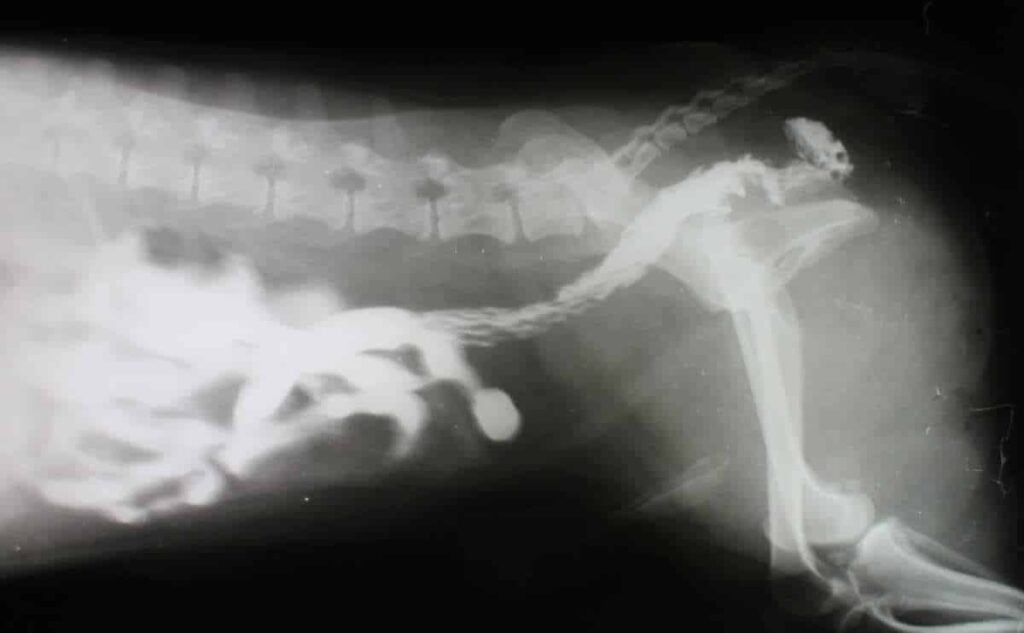

Sometimes the X-ray reveals the problem immediately. In other cases, the object only becomes clear once surgery begins.

Many clinics even keep photos of unusual foreign objects as reminders of just how unpredictable dogs can be.

See some examples here:

Stories like these might sound funny afterward, but the surgery required to remove them rarely is.